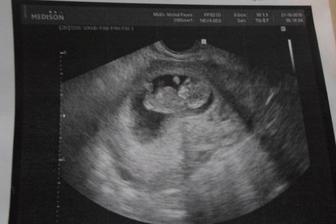

- 21.10.2015 - Kontrola, odběr krve, ultrazvuk a první fotka 🙂 Vše v pořádku, srdíčko krásně bije..